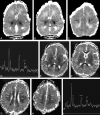

Results: In most of the patients a characteristic evolution of DTI and MR spectroscopy parameters was seen during the first 2 weeks after birth. Although the anatomic images were normal or nearly normal on the first 2 days after birth in most patients, abnormalities were detected on DTI (both visually and by quantitative interrogation of D(av) maps) and proton MR spectroscopy (abnormal metabolite ratios). These parameters tended to worsen until about day 5 and then normalize, though in several patients abnormal metabolite ratios persisted. Of interest, as areas of abnormal diffusivity pseudonormalized within one region of the brain they would develop in other areas. Therefore, the pattern of injury looked very different when imaging was performed at different times during this evolution.

Conclusion: Patterns of injury detected by standard anatomic imaging sequences, DTI sequences, and proton MR spectroscopy varied considerably during the first 2 weeks after injury. The appearance of new areas of reduced diffusion simultaneous with the pseudonormalization of areas that had reduced diffusion at earlier times can result in an entirely different pattern of injury on diffusivity maps acquired at different time points. Awareness of these evolving patterns is essential if studies are performed and interpreted during this critical period of time.